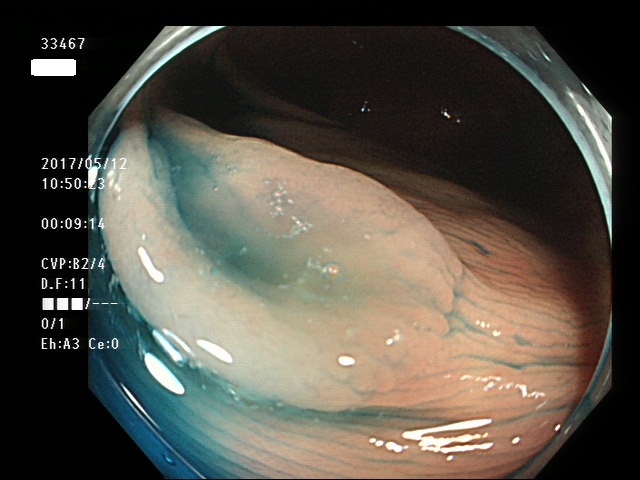

右側に大型の過形成(SSAP)が数個、多発する。SSAPが直接、癌化すると考えられている